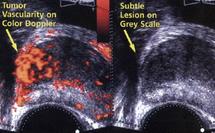

Pour le détecter dans les meilleurs délais, il est important de ne pas négliger certains symptômes comme l'envie d'uriner trop fréquente, notamment la nuit, un véritable blocage des urines et des douleurs osseuses. Ces symptômes doivent automatiquement entraîner une consultation qui permettra de détecter, ou non, la maladie. Pour ce faire, le médecin pourra utiliser plusieurs méthodes, de la simple interrogation du patient aux échographies et scanners, en passant par la palpation de la glande par l'anus et des tests sanguins vérifiant le bon fonctionnement rénal.